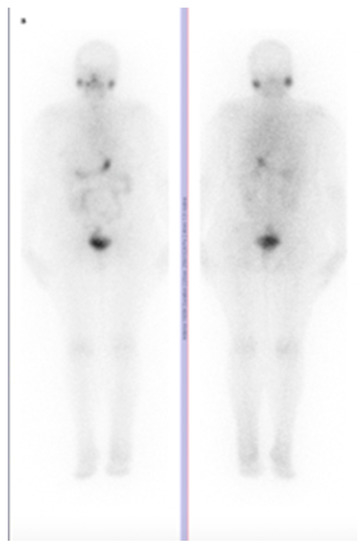

Skeletal Muscle Metastasis in Papillary Thyroid Microcarcinoma Evaluated by F18-FDG PET/CT

Hitu, L.; Cainap, C.; Apostu, D.; Gabora, K.; Bonci, E.-A.; Badan, M.; Mester, A.; Piciu, A. Skeletal Muscle Metastasis in Papillary Thyroid Microcarcinoma Evaluated by F18-FDG PET/CT. Diagnostics 2020, 10, 100. https://doi.org/10.3390/diagnostics10020100